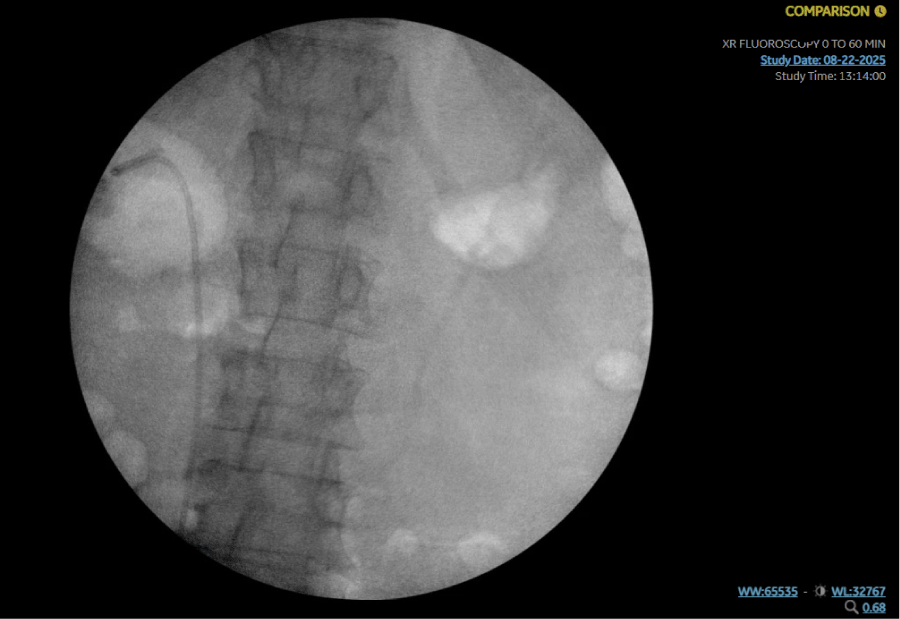

A 64-year-old woman with hypertension and gastroesophageal reflux disease presented with abdominal pain, nausea, vomiting, and fevers for 3 days. On admission, she was tachycardic (HR 110), with blood pressure 133/79 mmHg and temperature 38°C. Laboratory evaluation revealed leukocytosis (WBC 15.5 ×103/µL), lactic acidosis, and thrombocytopenia. Urinalysis was positive for infection with 20 WBC, 10-20 RBCs and Positive Leukocyte Esterase and Nitrites. CT abdomen and pelvis revealed an 8 × 4 mm proximal right ureteral stone with right-sided Uretral Stone and perinephric stranding (Figures 1 and 2).

Figure 1: CT abdomen/pelvis (axial) showing patchy right renal cortical enhancement and perinephric edema consistent with obstructive pyelonephritis. View Figure 1